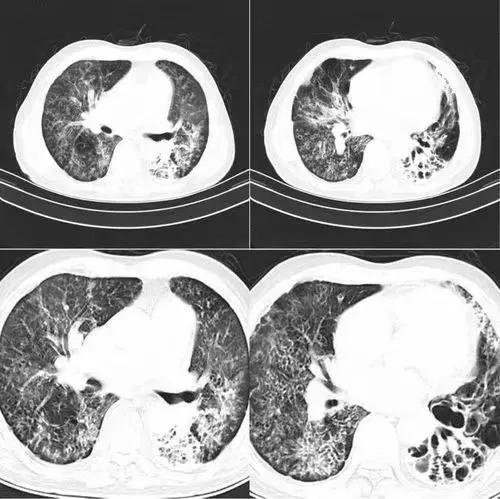

面對治療困境,患者懷揣著對康復的渴望,于數(shù)日前踏入鄭州西區(qū)中醫(yī)院(河南中醫(yī)院西區(qū)醫(yī)院)的大門,到呼吸科就診。通過胸部CT檢查,發(fā)現(xiàn)肺部有多處較大面積的陰影,被明確診斷為肺炎。鑒于病情嚴峻,患者隨即被安排入住醫(yī)院呼吸科病房,以期獲得更為全面深入的治療。

入院后,呼吸科許新主任和常二坡副主任醫(yī)師,急患者之所急,經(jīng)過反復討論,立即拿出了最佳的綜合治療方案。結合病情偏重,細菌侵襲力太強、大量粘痰難以咳出,以及常規(guī)的藥物治療好轉(zhuǎn)較慢、較難的情況,決定盡快啟用電子纖維支氣管鏡診療,以達到診斷更精準、療效又好又快的目的。